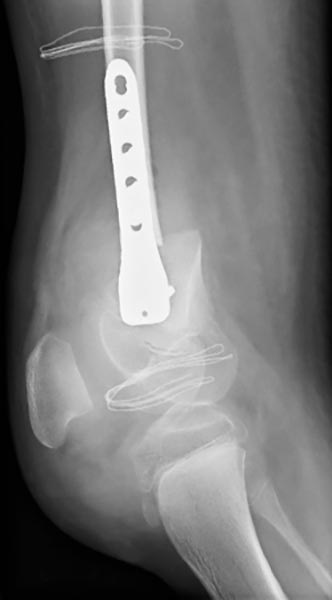

Durch eine operative Angleichung der Achse des Oberschenkels kann das Kniegelenk direkt postoperativ gestreckt werden. Fixation mittels einer Osteosynthese. Die Beinlängendifferenz konnte durch die gleichzeitige Entnahme eines Knochenkeils ausgeglichen werden.